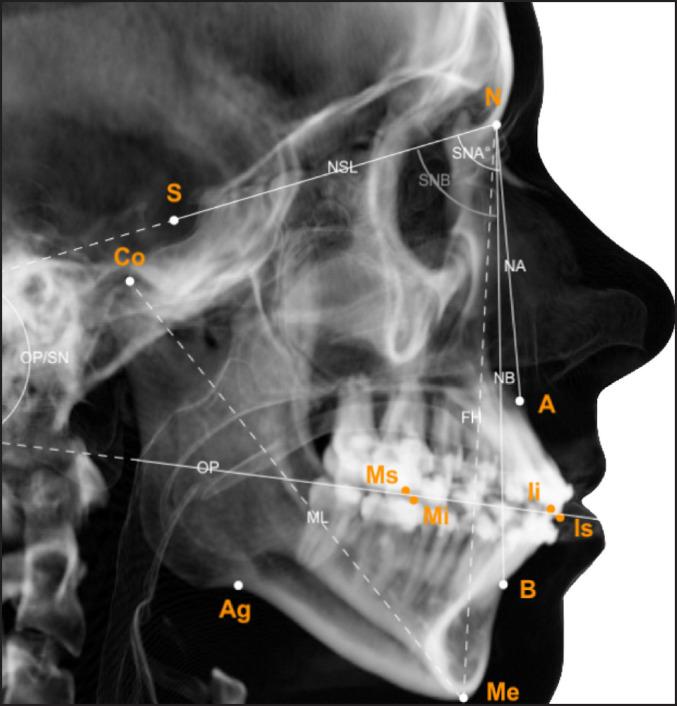

Nineteen patients with juvenile idiopathic arthritis of the temporomandibular joint (TMJ) and dentofacial deformities were included. All patients were treated with combinations of bilateral sagittal split osteotomy, Le Fort I and/or genioplasty, between September 10, 2007 and October 17, 2017. Analysis of patient symptoms and clinical registrations, and frontal/lateral cephalograms was performed pre- and postoperative and long-term (mean: 3.8 and 2.6 years, respectively).

Patients experienced no changes in orofacial symptoms or TMJ function, and stable normalisation of horizontal and vertical incisal relations at long-term (horizontal overbite; vertical overbite: P < 0.05). Mandibular lengthening was achieved postoperatively (from mean 79.7 to 87.2 mm; P = 0.004) and was stable. Sella-nasion to A point (SNA) and sella-nasion to B point (SNB) angles increased postoperatively (SNA, mean 79.9° to 82.8°; P = 0.022 and SNB, mean 73.9° to 77.8°; P = 0.003), however, largely reverted to preoperative status at long-term.

纳入19例患有颞下颌关节(TMJ)青少年特发性关节炎及牙颌面畸形的患者。2007年9月10日至2017年10月17日期间,所有患者均接受了双侧矢状劈开截骨术、Le Fort I型截骨术和/或颏成形术的联合治疗。在术前、术后及长期(平均分别为3.8年和2.6年)对患者症状、临床记录以及正侧位头影测量片进行分析。

患者的口面部症状或TMJ功能无变化,长期来看水平和垂直切牙关系稳定恢复正常(水平覆合;垂直覆合:P < 0.05)。术后实现了下颌延长(从平均79.7 mm增至87.2 mm;P = 0.004)且保持稳定。蝶鞍 - 鼻根至A点(SNA)和蝶鞍 - 鼻根至B点(SNB)角度术后增加(SNA,平均从79.9°增至82.8°;P = 0.022;SNB,平均从73.9°增至77.8°;P = 0.003),然而,长期来看大部分恢复到术前状态。